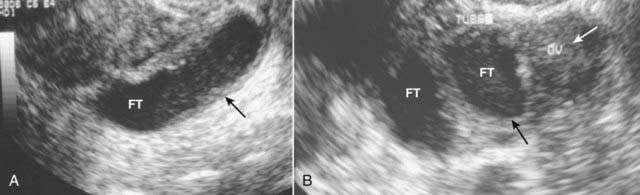

Pelvic Inflammatory Disease

image Pelvic inflammatory disease (PID) is a term used to describe a group of infectious diseases affecting the uterus, fallopian tubes, and ovaries. Most cases of PID begin as a transient endometritis and ascend to infection of the tubes and ovaries. Patients can have pain, vaginal discharge, adnexal tenderness and elevated white blood cell counts. Complications include infertility, chronic pain, or ectopic pregnancy.

image Recognizing PID on ultrasound

Enlarged ovaries with multiple cysts and periovarian inflammation

Fluid-filled and dilated fallopian tube (pyosalpinx) (Fig. 19-22A)

Fusion of the dilated fallopian tube and ovary (tubo-ovarian complex) (Fig. 19-22B)

Multiloculated mass with septations (tubo-ovarian abscess)

image

Figure 19-22 Pelvic inflammatory disease, sagittal and transverse views, US.

A, A fluid-filled and dilated fallopian tube (FT) containing pus and debris (solid black arrow) representing a pyosalpinx is demonstrated. B, Due to progressive inflammation, there is fusion of a dilated and tortuous fallopian tube (solid black arrow, FT) and the adjacent ovary (solid white arrow, OV) producing a tubo-ovarian complex.